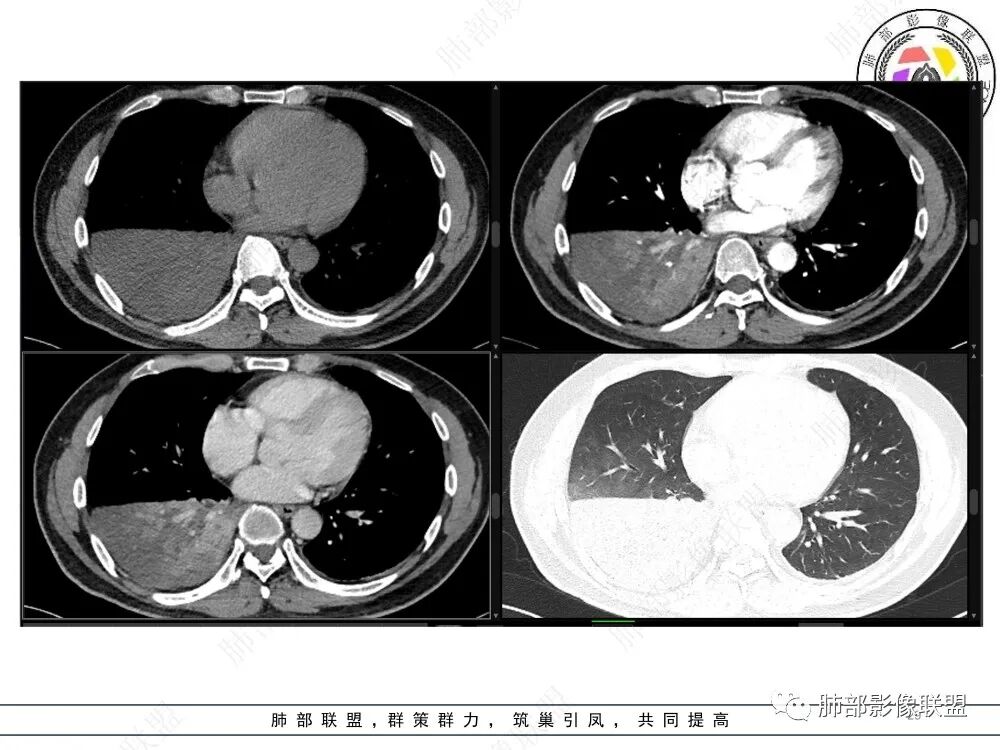

46岁男性,咳嗽、咳痰伴发热入院

血象和肿瘤指标升高

CT提示1、右肺下叶气管堵塞伴阻塞性肺不张,肺炎征象。2、破坏气管周边肿物可见结节样,肿物整体呈团块样

3、增强可见肿物明显强化。4、肿瘤内部血管可见破坏征象,但是破坏不完全。5.肿物坏死征象不明显。

定性:恶性肿瘤,破坏力不强。考虑肺腺癌?癌肉瘤?

三、病例结果

粘液表皮样癌

MEC是最常见的涎腺恶性肿瘤,占涎腺恶性肿瘤的30%,PMEC在原发性肺肿瘤中的发病率约为0.1%~0.2%。相关文献报道,PMEC的发病年龄多在30~40岁。

PMEC的临床表现无特异性,临床症状通常与肿块的大小、部位有关,肿块较小且位于外周者通常无任何症状,肿块较大且处于肺门时可引起呼吸道刺激及阻塞症状,如咳嗽、胸闷、喘息、咯血等。PMEC好发于大、中支气管,可引起呼吸道刺激和阻塞支气管管腔,继而引起阻塞性肺炎和肺不张。多数肿瘤密度不均匀,增强后强化程度不等,多数可见分叶及毛刺。

影像特点:

中心性起源:主要位于段及段以上支气管,多为气管、支气管腔内软组织结节及肿块,卵圆形或分叶状,沿支气管壁生长,最长径与支气管走行长径平行,与近心端支气管管腔呈钝角,支气管内可见“空气新月征”。

周围型MEC少见,且CT表现不具特征性,周围型结节或肿块,可出现分叶、毛刺等恶性征象,坏死、空洞较常见CT平扫多为欠均匀的低-中等密度,增强扫描后病灶以轻-中度不均匀强化为主。

肿块内钙化:MEC较其他类型肺癌钙化率高,约50%病例中可见斑点或颗粒状钙化。钙化可能与病程较长,局部血供少致营养不良性钙化有关,肿瘤支气管远端可出现阻塞性肺炎及肺不张征象。